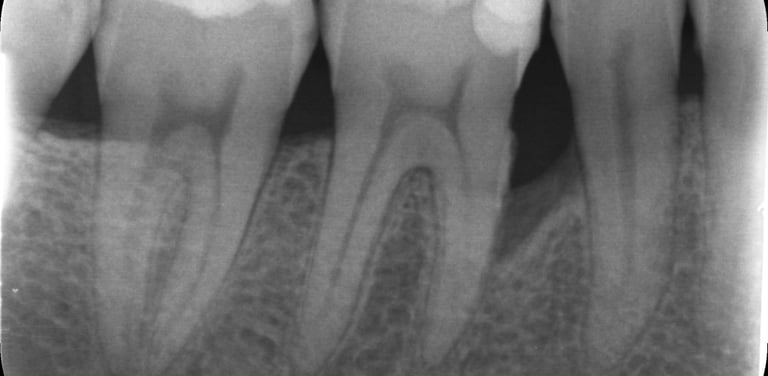

Grâce aux vignettes cliniques, vous découvrirez des situations et radiographies concrètes, vous permettant d’appliquer directement ces recommandations dans votre pratique quotidienne.